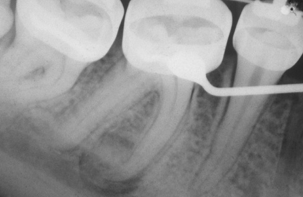

periapical cemento-osseous dysplasia